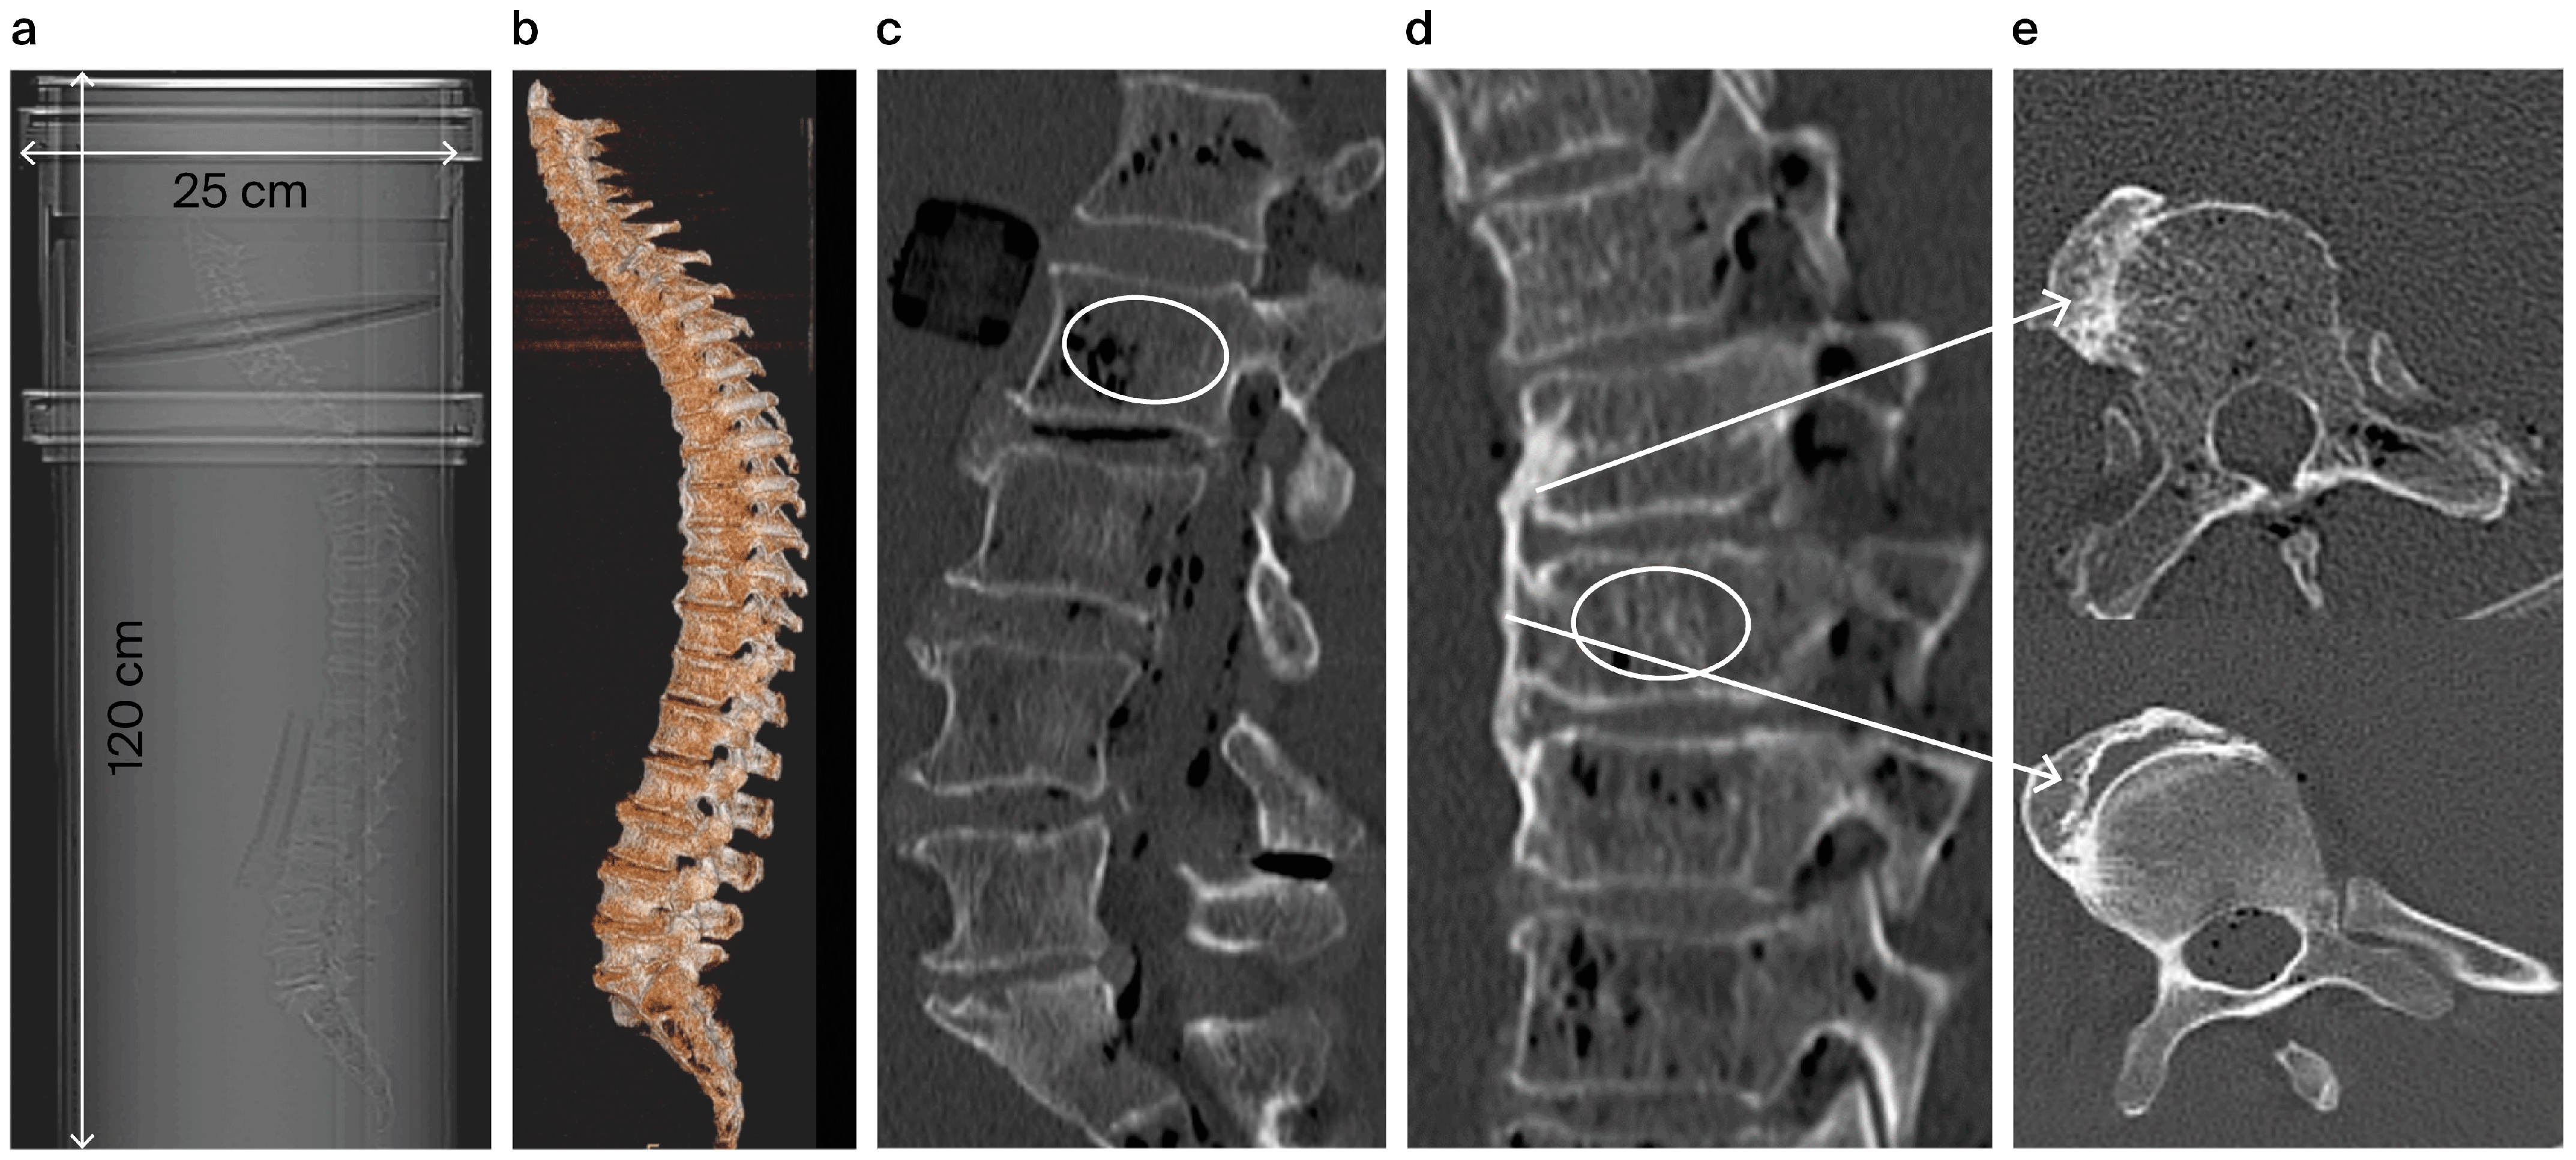

2. Medical History

3.3. Diagnostic Imaging CT and QCT

3.4. Micro-CT Imaging